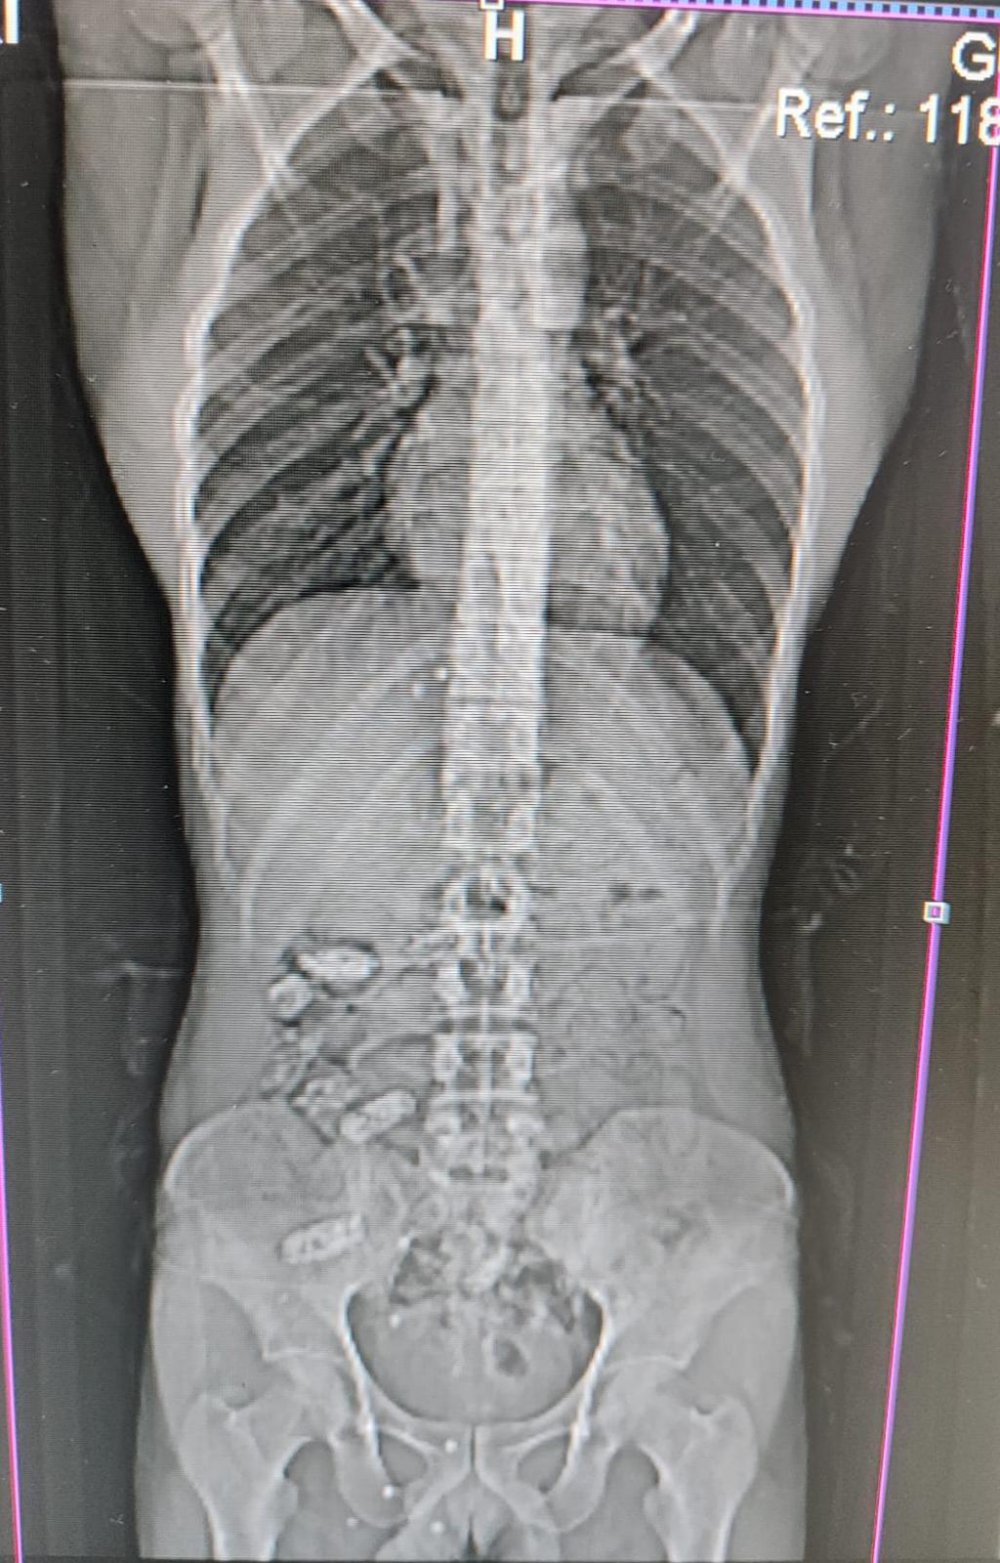

Burada yapılan kontrollerinde ve çekilen röntgen filmlerinde S.A’nın midesinde uyuşturucu madde olduğu tespit edilince hastanede yapılan müdahaleler sonucunda bu maddeler çıkarıldı.

Operasyonda S.A’nın midesinde toplamda 18 adet kapsül halinde 152,29 gram metamfetamin maddesi ele geçirilirken yabancı uyruklu şahıs hakkında Uyuşturucu Madde İmal ve Ticareti suçundan adli makamlarca tutuklanarak cezaevine gönderildi.